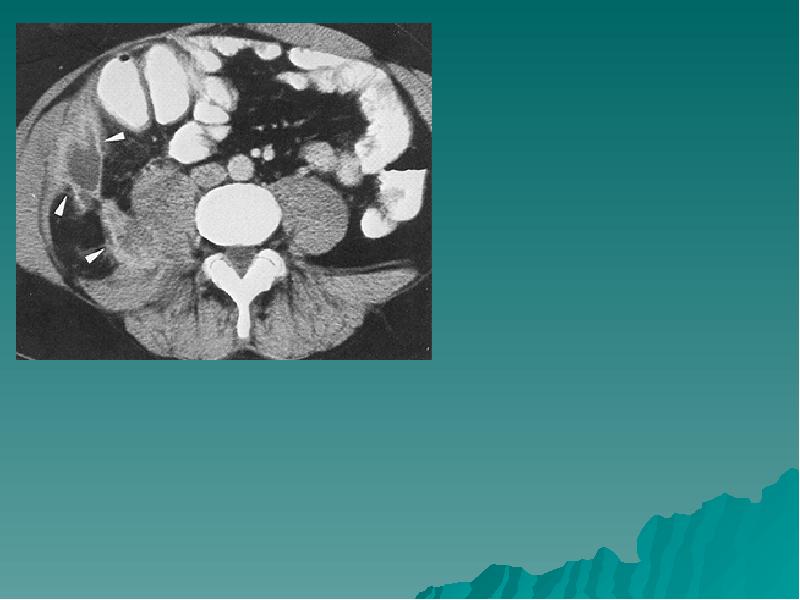

КТ диагностика тубоовариального абсцесса: Подходы и изображения

Раздел: Объективный взгляд